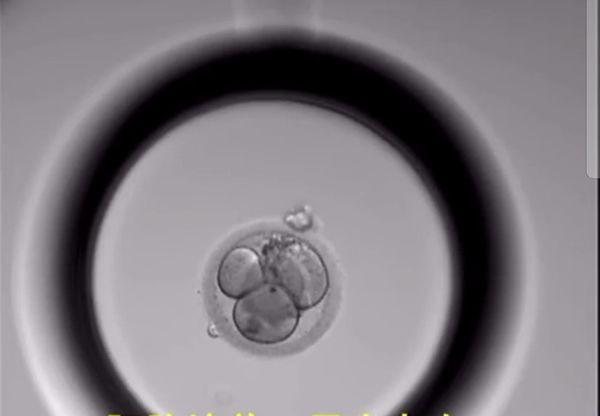

胚胎培养第2天:胚胎开始分裂为2-4细胞胚胎

胚胎培养第3-4天:胚胎开始分裂为4-8细胞胚胎,鲜胚移植就是用这个时期的胚胎宝宝。